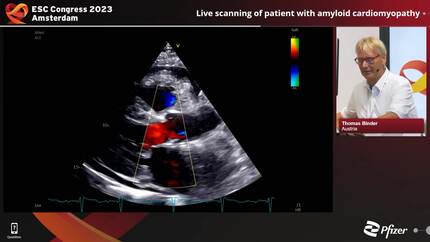

Professor T. Binder (Vienna, AT)

Medical University of Vienna, Vienna (Austria)

ESC Congress 2023

25 August - 28 August 2023